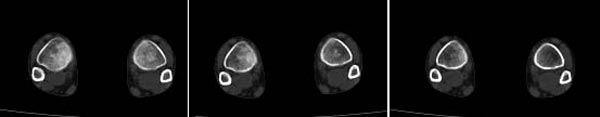

x线检查月前片示双踝关节骨质未见明显异常。一月后肿胀大部消失,疼痛稍有好转,摄片示两侧骨下段条带状高密度影,边界尚清。ct扫描示两侧胫骨下段骨皮质增厚不明显,髓腔内密度显示磨玻璃样增高,髓腔显示狭窄。

x线检查一个月前示双踝关节骨质未见异常。一个月后肿胀大部消失,疼痛稍有好转,摄片示两侧胫骨下段横行条状高密度影,边界较清。ct扫描示:两侧胫骨下段未见骨皮质增厚,两胫骨下段近骨端处可见骨小梁增粗但纹理尚清晰,未见明显骨质破坏,邻近关节及关节囊未见明显异常,软组织内未见异常.综上所诉考虑1.低毒感染所致,2.假性痛风

x线片表现为双侧胫骨下端粗条状磨玻璃样增高密度影,并可见骨皮质稍不连续。ct表现为双侧胫骨下端髓腔内磨玻璃样增高密度影,未见明显骨皮质不连续(可能与扫描体位有关)。